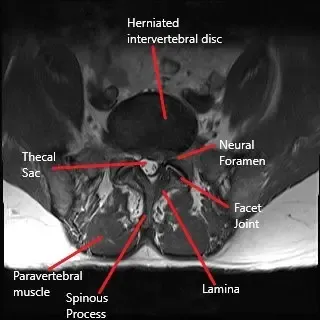

El dolor de espalda y la radiculopatía pueden limitar la intimidad física del paciente, hasta el punto de que puede dejar de tener actividad sexual. La microdiscectomía es una cirugía de referencia para aliviar los síntomas de la radiculopatía lumbar debida a una hernia de disco intervertebral. Sin embargo, un síntoma que normalmente no se comenta tras la cirugía es la reanudación de la intimidad sexual.

Una vida sexual saludable es un predictor esencial del bienestar del paciente. El dolor de espalda con radiculopatía debido a una hernia de disco intervertebral suele dificultar la vida sexual del paciente. El dolor durante la actividad sexual, así como la anticipación del dolor, influyen en la insatisfacción durante el sexo. Algunos pacientes pueden dejar de tener toda actividad sexual debido a molestias, lo que solo puede aumentar el aspecto emocional del dolor radicular de espalda.

La cirugía de microdiscectomía es una cirugía mínimamente invasiva que se realiza con un microscopio operatorio o un endoscopio. La naturaleza mínimamente invasiva de la cirugía reduce la reducción de los cortes musculares y tejidos al acceder al disco. La incisión más pequeña también reduce la formación de tejido fibrótico tras la cirugía. Los pacientes que se someten a una microdiscectomía pueden volver al trabajo y a sus actividades diarias antes que en una cirugía de enfoque abierto.